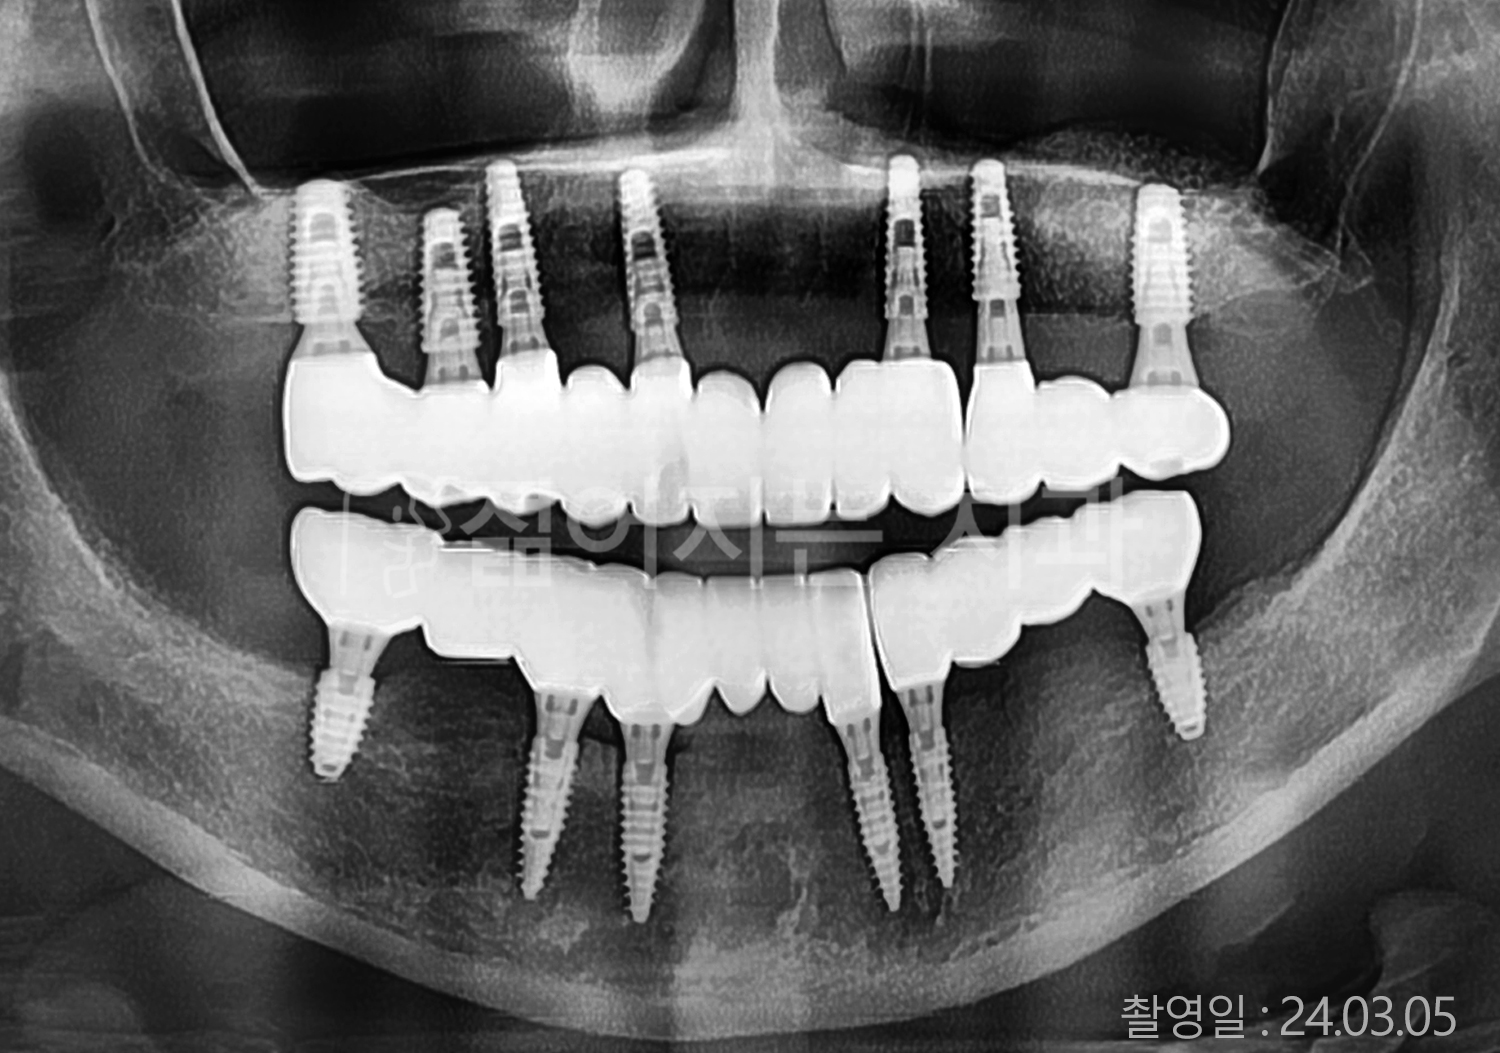

• 70대 고혈압, 당뇨 전체치아 10개 이상 임플란트

• 50대 고혈압, 당뇨 전체치아 10개 이상 임플란트

• 60대 고혈압, 당뇨 전체치아 10개 이상 임플란트

• 50대 전체치아 10개 이상 임플란트

• 70대 당뇨 전체치아 10개 이상 임플란트

• 80대 전체치아 10개 이상 임플란트

• 40대 전체치아 10개 이상 임플란트

• 60대 고협압, 고지혈증 전체치아 10개 이상 임플란트

• 60대 전체치아 10개 이상 임플란트